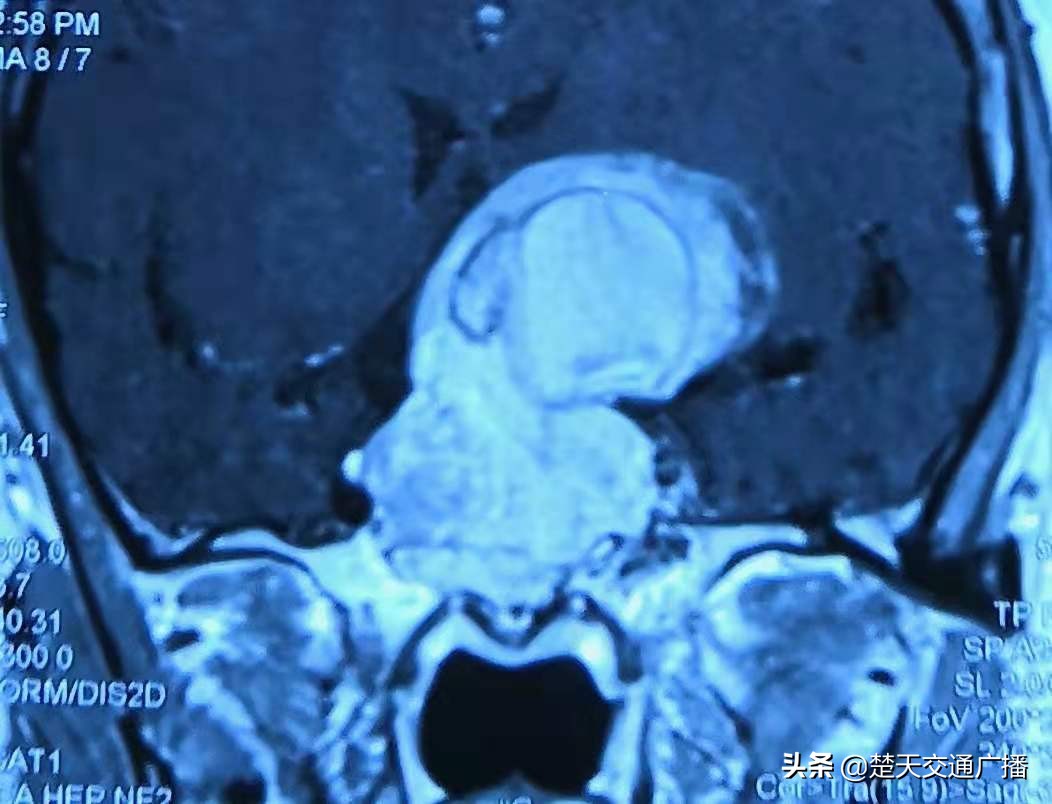

经详细查体与MRI检查,叶女士确诊为脑垂体瘤,肿瘤大达6.3cm×5.8cm,似成年女性拳头大小。“患者脑垂体瘤体积巨大,并严重压迫视神经、侵及下丘脑、海绵窦,包绕颈内动脉,需尽快进行手术,不然危及生命。”姜主任介绍肿瘤已侵入叶女士脑部的重要区域,相当于占领了人体的“司令部”,这使手术富有挑战。

患者术前CT